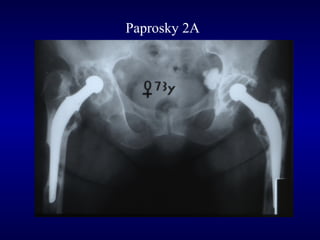

Paprosky 2A

Tipo 2A